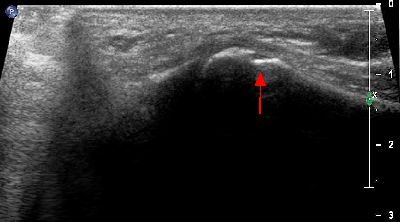

Becco osteofitico della 1a articolazione metatarso-falangea becco osteofitico prima metatarso-falangea